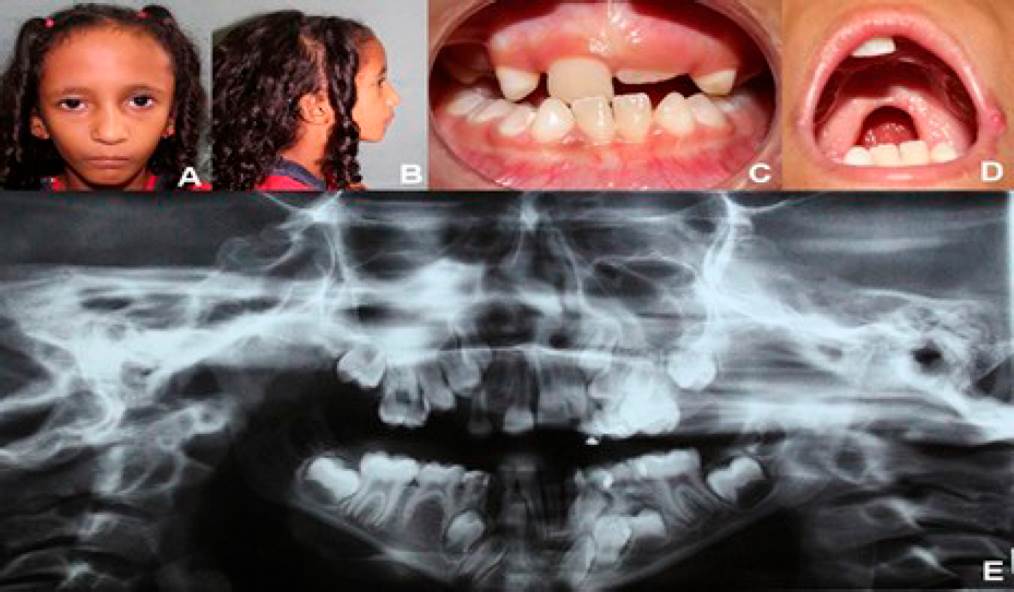

Paciente del género femenino, ocho años de edad, con síndrome de Silver-Russell; nacimiento a las 38 semanas de gestación, con bajo peso (1,225kg). Permaneció internada a nivel hospitalario por tres meses para aumentar de peso ponderal, por lo que fue necesaria la alimentación suplementaría (NAN®, Nestlé S.A, Vevey, Suiza) además de la leche materna, y su alta hospitalaria fue al alcanzar 1,850kg de peso. En junio de 2014, fue internada para soporte nutricional y ganancia de peso, mientras se planeaba cirugía correctiva de la fisura palatina, período en el que se confirmó el diagnóstico del síndrome. Desde entonces, la madre de la paciente refiere dificultades para ganar peso, a pesar de una alimentación proporcional y adecuada para la edad. Durante el examen físico actual se identificó baja estatura y bajo peso, discreta asimetría en tórax, con pezón derecho más alto que el izquierdo y expansibilidad preservada, clinodactilia en quinto dedo, asimetría en relación al tamaño de las manos y miembros superiores. La paciente no presenta déficits neurológicos y psicomotores, sin embargo, sí dificultades para la fonación, con habla hipernazalizada en respuesta a la insuficiencia velofaríngea. Se encontraba bajo tratamiento de Enzima Pancreatina 10000 UI por indicación del endocrinólogo asistente. Con el examen físico maxilofacial, se observó una desproporción de los tercios faciales, con frente prominente y rostro triangular, baja implantación de las orejas, nariz voluminosa, buena abertura bucal, presencia de hendidura palatina post-foramen completa, mordida cruzada anterior y posterior, agenesia dentaria, paladar ojival y buena higiene oral (Figura 1.A-E). Considerando la historia familiar, se sospecha que la hermana mayor de la paciente reúne varias condiciones del mismo síndrome y se encuentra en análisis esperando diagnóstico. La paciente se encuentra en programación para cirugía correctiva de la hendidura palatina, para poder recuperar el peso necesario. Se propondrá acompañamiento clínico-ortodóntico para tratar atresia de los maxilares.

Figura 1 Fotografías del caso clínico. A. Vista frontal evidenciando rostro triangular, con desproporción entre los tercios faciales y micrognatia. B. Vista lateral: frente prominente e implantación baja de las orejas. C. Vista frontal oclusal: mordida cruzada anterior y posterior, agenesia y atraso en la erupción dentaria. D. Vista intraoral: Presencia de hendidura palatina post-foramen completa. E. Ortopantomografía mostrando atraso de erupción dentaria, impactación y agenesia.